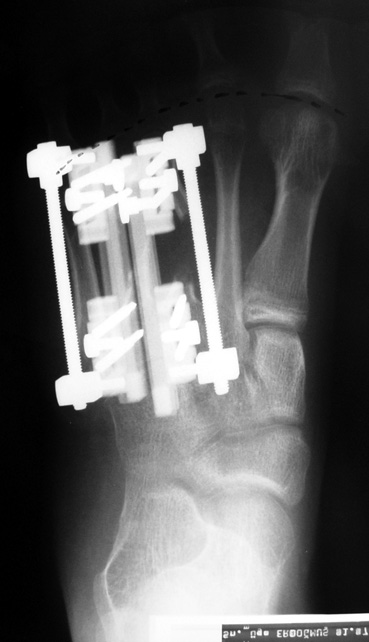

Doğuştan metakarp ve metatars kısalıklarının redavisi için pek çok teknik tanımlanmakla birlikte en çok akut uzatma sonrası kemik uçlarına greft konması ve distraksiyon osteogenezi (kallotasis) kullanılmaktadır. 1 cm.den daha fazla uzatma gereken olgularda kallotasis yöntemi önerilmektedir. Kliniğimizde de metatars ve metakarp uzatma için unilateral eksternal fiksatör ve sirküler eksternal fiksatör yardımıyla distraksiyon osteogenezi yöntemi tercih edilmektedir.